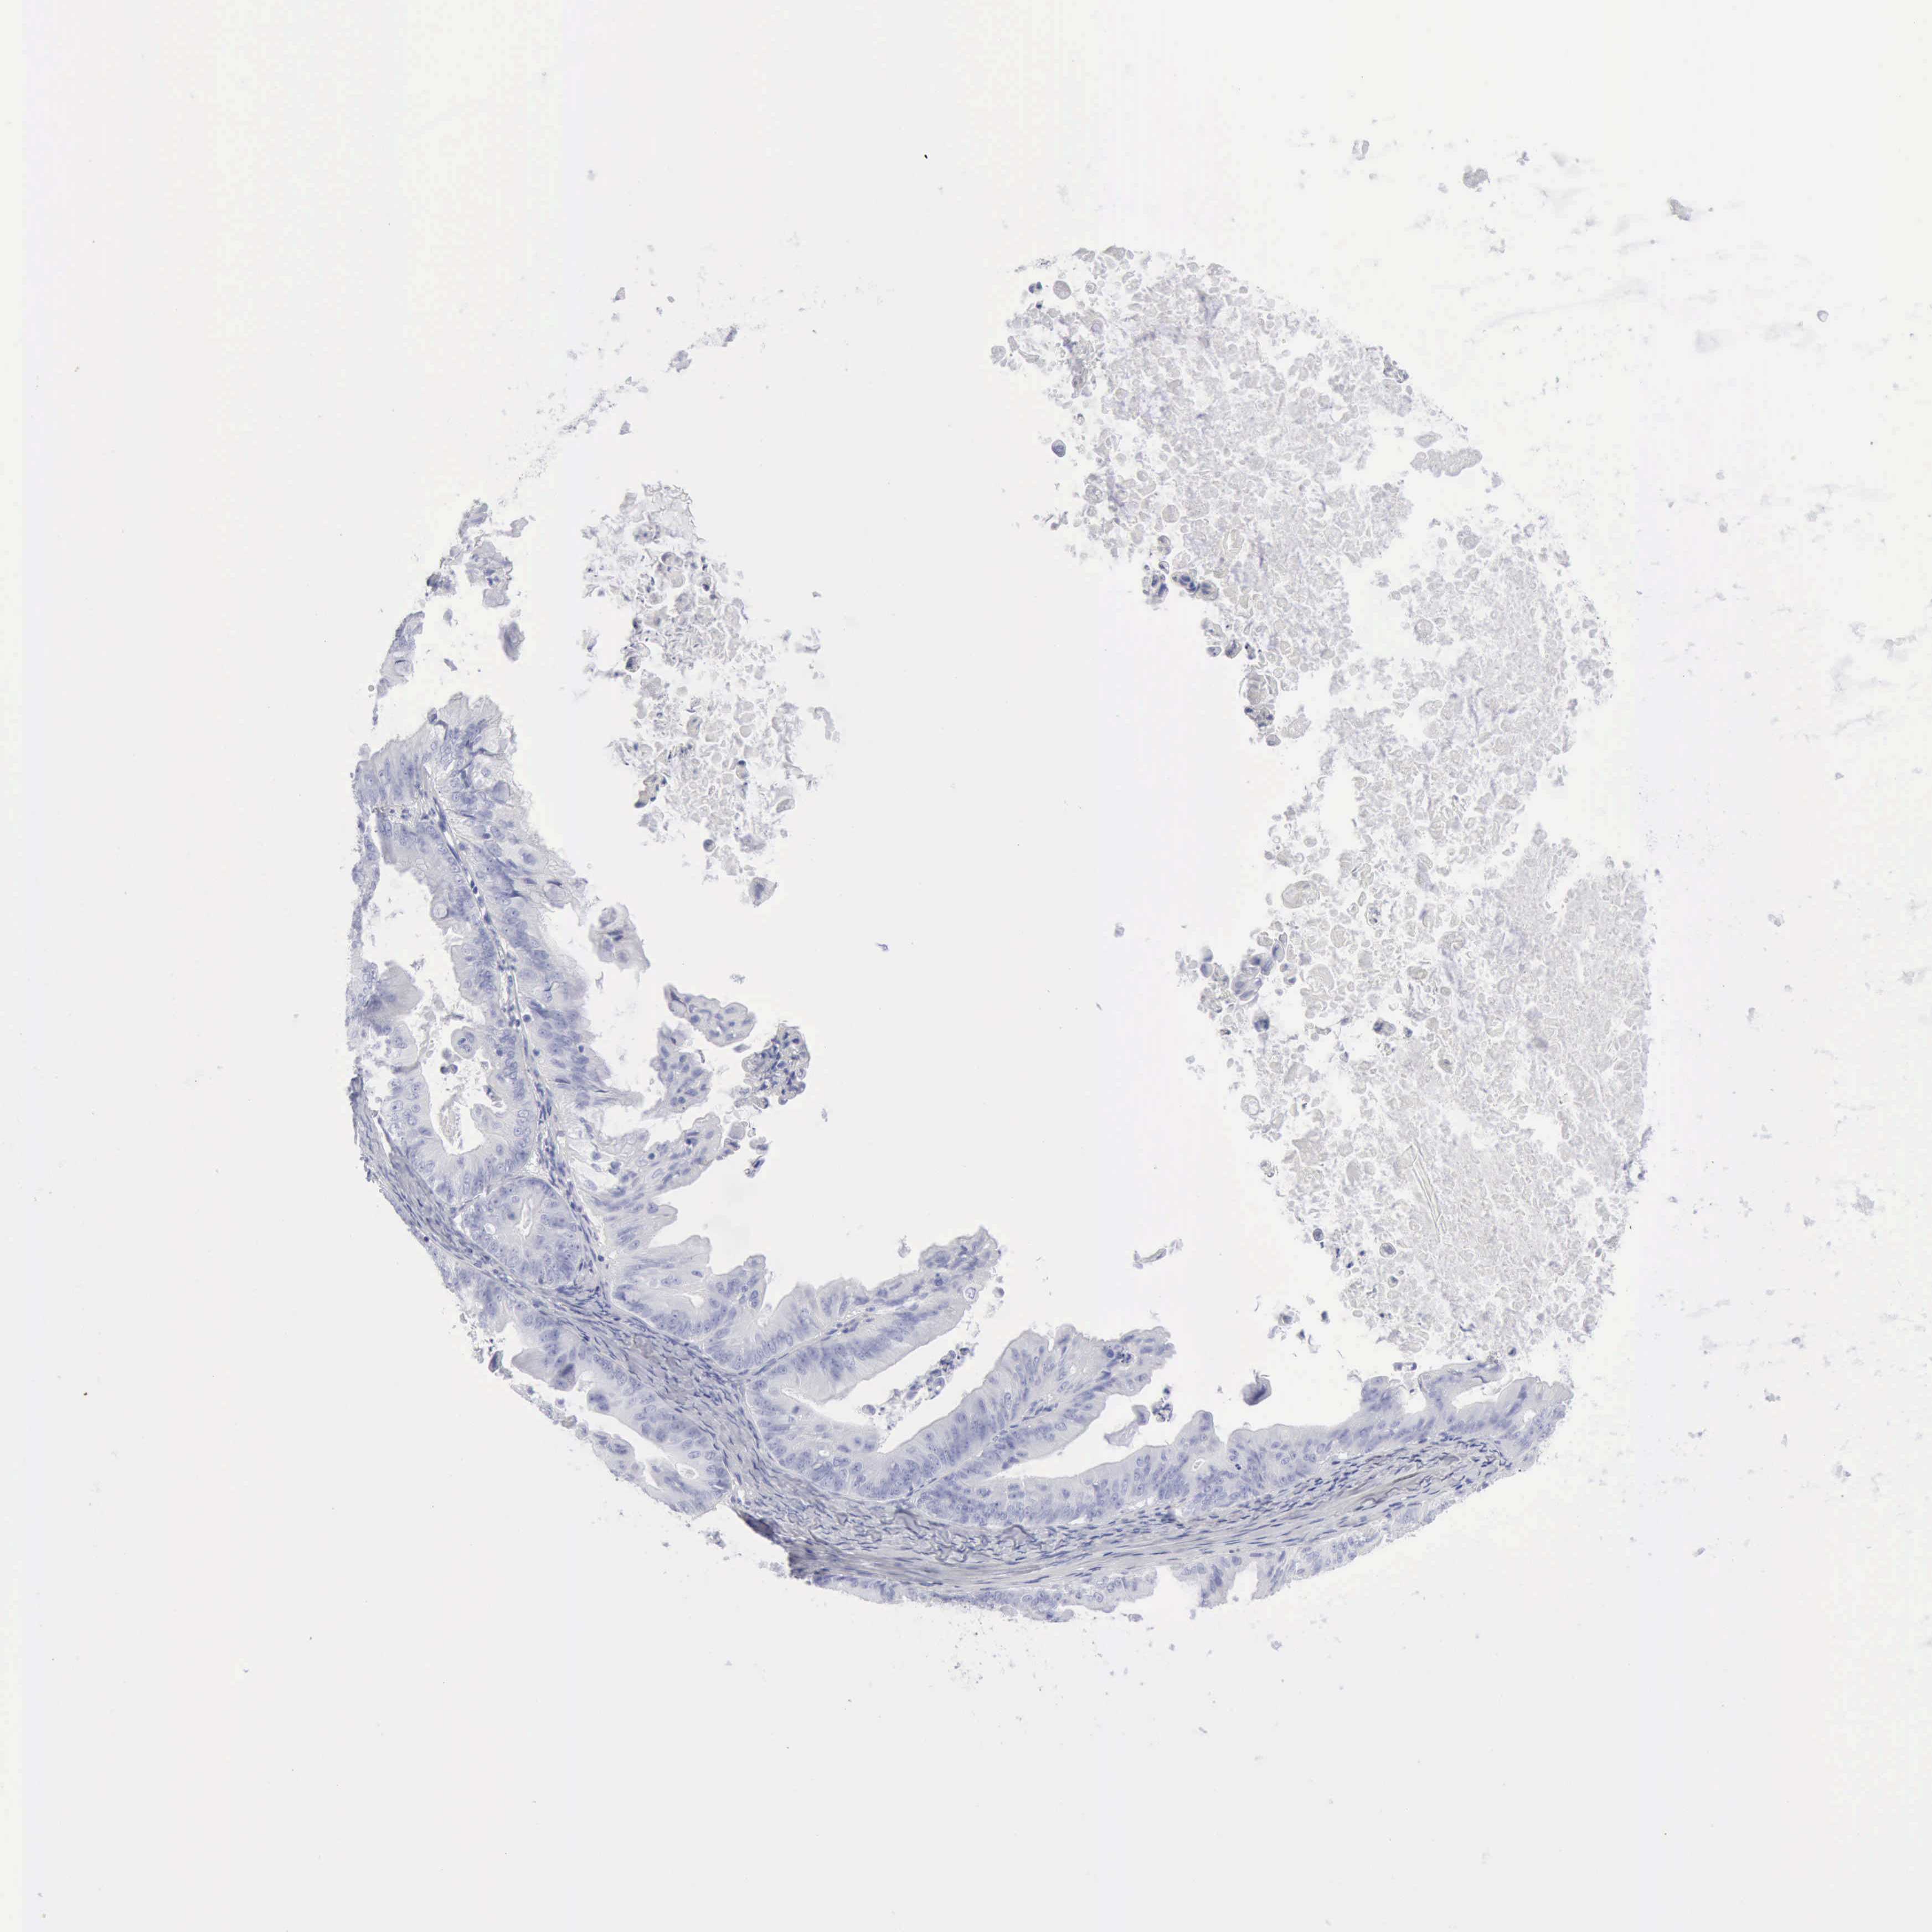

OVARIAN CANCER - Protein expressioni

A mouse-over function shows sample information and annotation data. Click on an image to view it in a full screen mode. Samples can be filtered based on level of antibody staining by selecting one or several of the following categories: high, medium, low and not detected. The assay and annotation is described here.

Note that samples used for immunohistochemistry by the Human Protein Atlas do not correspond to samples in the TCGA dataset.

Antibody stainingi

Antibody staining in the annotated cell types in the current human tissue is reported as not detected, low, medium, or high, based on conventional immunohistochemistry profiling in selected tissues. This score is based on the combination of the staining intensity and fraction of stained cells.

Each image is clickable and will lead to virtual microscopy that enables deeper exploration of all samples and also displays staining intensity scores, fraction scores and subcellular localization as well as patient and tissue information for each sample.

Antibody HPA012014

Antibody CAB000132

Staining

High

Medium

Low

Not detected

Intensity

Strong

Moderate

Weak

Negative

Quantity

>75%

75%-25%

<25%

None

Location

Nuclear

Cytoplasmic/membranous

Cytoplasmic/membranous,nuclear

Cystadenocarcinoma, serous, NOS

Cystadenocarcinoma, mucinous, NOS

Carcinoma, endometroid